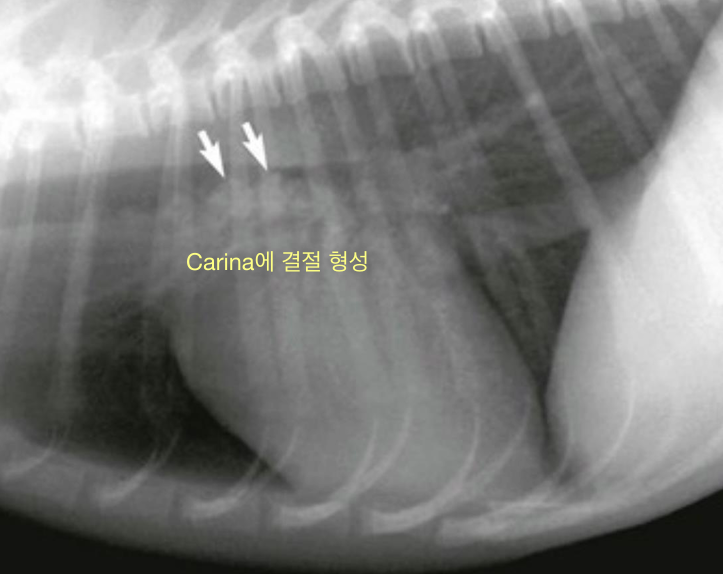

➕ Oslerus Osleri (기생충)

- 2살 이하의 어린 개에서 발견되는, 흔하지 않은 기생충.

- Carina나 bronchi에 서식.

- acute, large dry cough / wheezing

- 초기에는 CIRDC와 구분 어려움. but carina에 결절이 형성되며 결국 airway obstruction을 나타내는 차이점.

- 진단

- 방사선 촬영 - carina의 nodules

- bronchoscopy로 결절 가장 잘 보임.

- tracheal wash에서 ova or larvae 관찰.

- 구충을 잘 해주고 있고, fenbendazole 먹으면 금세 치료되기 때문에 큰 병은 아님.